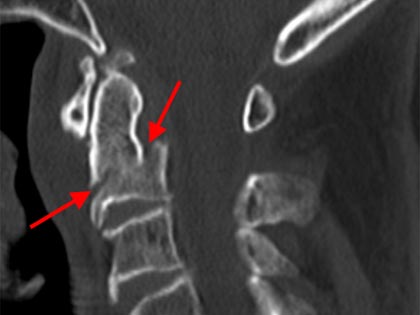

Schmerzsyndrome der Wirbelsäule; Bandscheibenvorfall; Verschleiß der Bandscheiben; Spinalkanalstenose (Verengung des Wirbelkanals); Instabilitäten; Spondylolisthesis (Wirbelgleiten), Myelopathie (Schädigung des Rückenmarkes); Querschnittslähmung; Erkrankungen bei Kinder und Heranwachsenden (z. B. Formveränderungen, Skoliosen, Kyphosen, angeborene Wachstumsstörungen, Verletzungen, Entzündungen, Tumore und Metastasen); Verletzungen des Rückenmarks; Wirbelkörperbrüche; Deformitäten (Formveränderungen, Skoliose, Kyphose); Tumore und Metastasen; Infektionen; Spondylodiszitis (Infektion von Bandscheiben und Wirbelkörper); rheumatische Instabilitäten der Halswirbelsäule sowie zwischen Kopf und Halswirbelsäule; rheumatische Veränderungen der Brust- und Lendenwirbelsäule (z. B. Morbus Bechterew);Verengungen des Foramen magnum; muskulärer Schiefhals; Syndrome durch die erste Rippe; Deformitäten des Thorax (z. B. Trichterbrust, Kielbrust); Erkrankungen und Verletzungen der Rippen; etc.